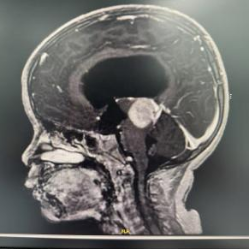

患儿术后MRI图像

术后病理考虑为颅内间叶源性肿瘤,非脑膜上皮来源。FISH提示EWSR1不典型断裂阳性。术后MRI显示肿瘤完全切除。目前患儿情况稳定,由ICU转入普通病房。

患儿术后MR影像:松果体区肿瘤组织切除完全